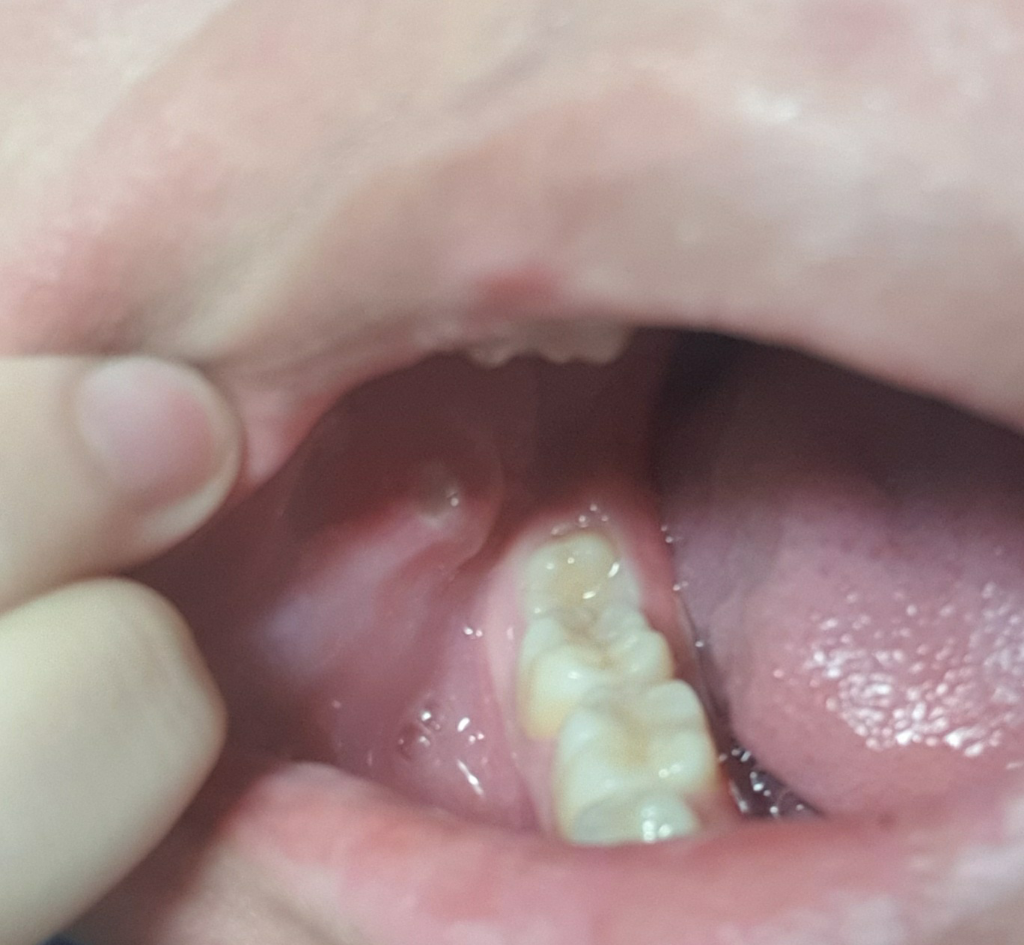

입 안에 혹이 생겼는데 구내염인가요 구강암인가요?

평소에는 아무것도 없이 너무 멀쩡하다가 갑자기 자고 일어났는데 저런게 생겼어요.ㅠㅠ발생한 후로부터 지금 한 2~3일 정도 지난 상태고 그동안 제가 이물감에 혀로 몇번 두드리니까 더 심해진 것 같기도 해요. 잘때나 일상생활 할 땐 통증이 없는데 밥먹을땐 아무래도 음식이 닿아서 그런지 통증이 있긴 하더라구요. 인터넷에서 보니까 입안에 혹이 생기면 구강암이라고 하던데 맞는건가요? 꾸준한 가글과 양치질로는 해결할 수 없는건가요?

• 1번 째 사진

현재 상태에서는 구강암으로 의심되지는 않습니다. 단순 구내염이거나 구강 내 연조직 질환일 가능성이 있습니다. 현재 상태에서는 가글은 추천드리지 않으며 양치를 해보시길 바랍니다. 단순 구내염이라면 2주 정도의 시간은 필요합니다. 다만 2주가 지나도 해당 병소가 사라지지 않고 통증이나 불편감이 커진다면 이때는 감별진단을 받아보셔야 합니다.

아무래도 저부분은 치아에 씹힌부분에 계속 자극이 가해져서 그런거 같습니다. 쉽게 말해서 상처가 자극을 받아서 구내염처럼 된거 같아요. 시간이 지나면괜찮아 지니 크게 걱정할부분은 아닙니다.

구내염으로 보이며 시간이 경과하면 호전되는 경우가 많습니다.